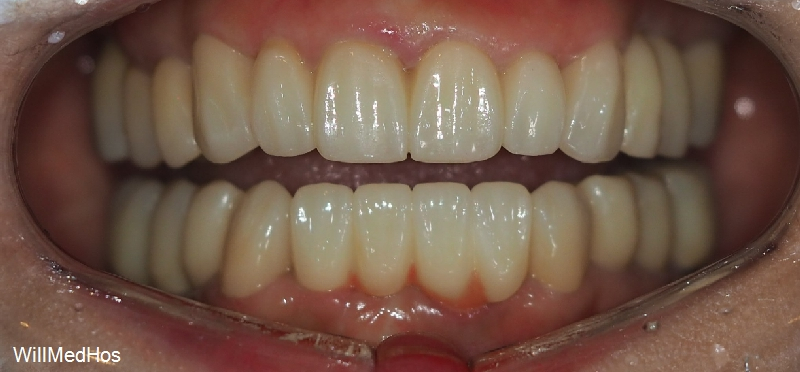

최종 치료 완료된 구강 모습입니다. 앞전의 구강 사진과 비교해보시면 자연스러운 치아의 모습이 완성된것을 확인 할수 있습니다.

전체 최종 치료 기간은 9개월 소요 되었습니다

환자분은 사람들과 많이 대면하고 이야기 해야 하는 서비스 직이라 그때마다 불편하셨는데

지금은 너무 편하게 지내고 있기도 하고 치료과정과 결과도 너무 만족 스러워 하셔서

저희가 너무 뿌듯할 따름입니다.